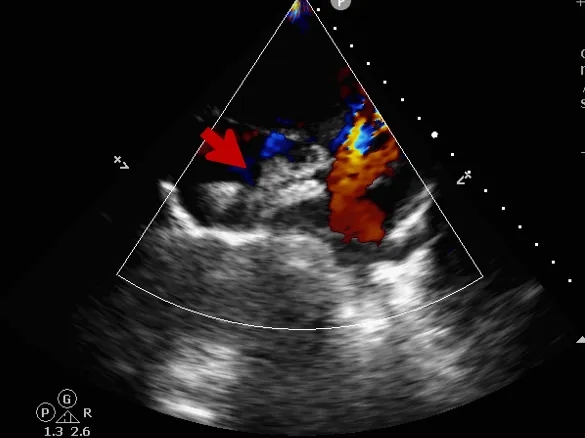

锁定后评估

心尖四腔心切面可见封堵器形态良好

主动脉短轴切面可见封堵器呈“Y”字型抱住主动脉

彩色多普勒血流成像显示无残余分流存在

释放后评估

封堵器位置正确、形态良好

封堵成功